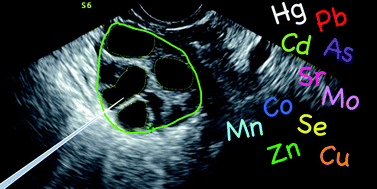

Follicular fluid (FF), which is the fluid that envelops the developing oocyte (egg cell) in the ovary, can be analyzed to assess trace element content as well as to determine potential exposure to toxic elements in women seeking in vitro fertilization (IVF) treatment. Such measurements may be useful in establishing associations with potential adverse effects on oocyte viability and subsequent pregnancy outcomes. The principal goal of this study was to leverage the next generation of inorganic mass spectrometry based on ICP-MS/MS to address the numerous analytical challenges of (ultra-)trace element analysis of human FF specimens. Ultra-trace element measurements are defined by the Clinical Laboratory Standards Institute as fluid concentrations below 10 μg L−1 or tissue mass fractions below 1 μg g−1. Stringent pre-analytical procedures were developed to minimize exogenous contamination during FF specimen collection and storage in a prospective study of 56 women seeking IVF treatment. ICP-MS/MS instrumental parameters were carefully optimized, and the method validated for 11 biologically important elements that included 4 at trace levels (Cu, Se, Sr, and Zn) and 7 at ultra-trace levels (As, Cd, Co, Mo, Mn, Hg, and Pb). Method limits of detection (LODs) for ultra-trace elements varied from 5.6 ng L−1 for Cd to 0.11 μg L−1 for Mo. A total of 197 human FF specimens were analyzed using the proposed ICP-MS/MS method with 84% of specimens detectable for Pb and 100% detectable for Co, Cu, Mn, Mo, Sr, and Zn. The method based on ICP-MS/MS was compared to a previous method developed for FF using SF-ICP-MS.